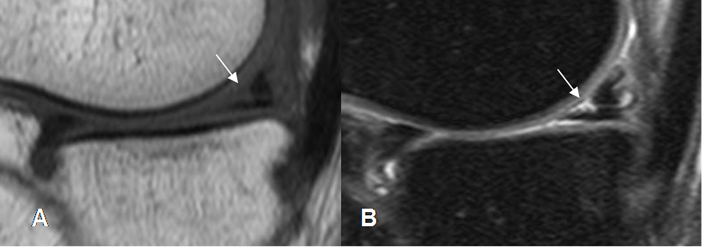

Fig 74. Ruptura meniscal oblicua.

A: RM sagital en T1 y B: RM sagital en STIR. Imagen en sentido oblicuo, que se comunica con la superficie articular inferior, por ruptura meniscal.